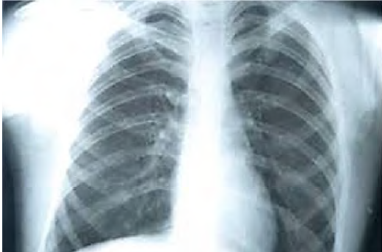

Um paciente etilista deu entrada no pronto-socorro com intensa dor na região torácica, associado a vômitos, após realizar grande esforço. A dor é localizada na região retroesternal e em abdome superior, de início agudo e de forte intensidade. Quanto a comorbidades, informa tratamento para úlcera gástrica há um ano. Queixa-se de odinofagia associada ao quadro de dor no peito. Ao exame físico, constatam-se abdome doloroso sem sinal de irritação peritoneal, PA = 150 mmHg x 100 mmHg, FC = 130 bpm, FR = 30 irpm e SatO2 = 93% AA. Realizou raios X de tórax, representado na imagem a seguir.

Disponível em: <https://www.tuasaude.com/>